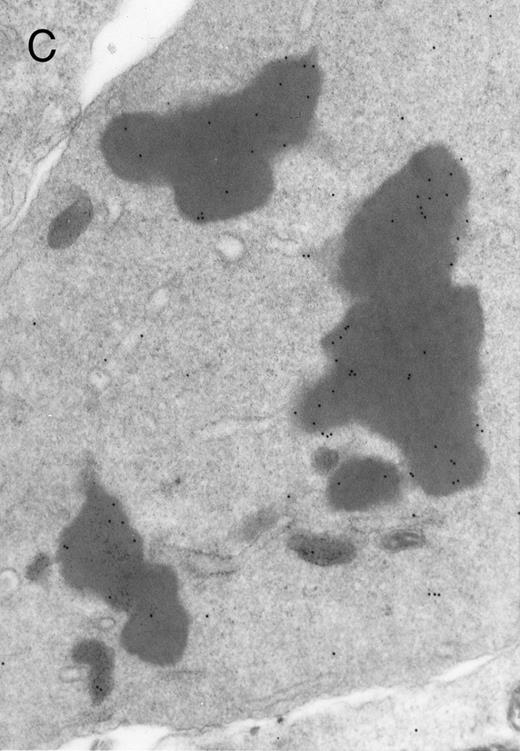

In both cases no. 1 and no. 2, electron microscope studies demonstrated electron-dense inclusions in 30% of early and late polychromatic erythroblast sections and many marrow reticulocytes. In ultrathin sections that reacted with monoclonal antibodies to either α- or β-globin chains followed by gold-labeled anti-mouse IgG, the density of gold particles over the majority of the inclusions was clearly greater than that over surrounding inclusion-free cytoplasm (Fig 3). By contrast, in sections from the two patients with β-thalassemia major, gold particles were concentrated over the inclusions following incubation with the antibody to α-globin chains, but not to β-globin chains (Fig 4A-C). The density of gold particles over inclusions in all control preparations was not greater than that over surrounding cytoplasm (Fig 4D).

Electron micrographs of erythroblastic inclusions from sections of marrow immunogold-labeled with mouse monoclonal antibody. Inclusions from a case of β-thalassemia major show a positive reaction with antibody against human α-globin chains (A, B) and no reaction with antibody against human β-globin chains (C). B shows part of the inclusion in A at higher magnification. There is virtually no labeling of inclusions in a control section that was reacted with normal mouse serum instead of a monoclonal antibody (D). Magnifications: A, × 20,000; B, × 59,000; C, × 23,000; D, × 35,000.

Prominent intra-erythroblastic inclusions were also present in both of these individuals (patients no. 1 and 2) with dominantly inherited β thalassemia. The percentage of polychromatic erythroblast sections containing inclusions in the two cases was 30%, which is considerably above the range (0.2% to 2.8%) previously reported in β-thalassemia trait.13 We have investigated the composition of the inclusions in cases no. 1 and 2 by immunoelectron microscopy using mouse monoclonal antibodies against human α- and β-globin chains and the immunogold technique. The intra-erythroblastic inclusions in the two cases reacted with both monoclonal antibodies to α- and β-globin chains, clearly indicating that these inclusions contained both types of chains. In contrast, the intra-erythroblastic inclusions found in homozygous β thalassemia reacted with the monoclonal antibody against α globin but not β-globin chains, confirming that they consisted only of precipitated α-globin chains. These data support the hypothesis that the cellular pathology underlying the dominantly inherited β thalassemias is related to the synthesis of highly unstable β-globin chains, which are not able to form functional tetramers. These abnormal β-chain variants precipitate intracellularly together with the concomitant excess α-globin chains to form large inclusions, which leads to more severe ineffective erythropoiesis than in heterozygous β thalassemia, in which much smaller amounts of precipitated globin chains are found.17